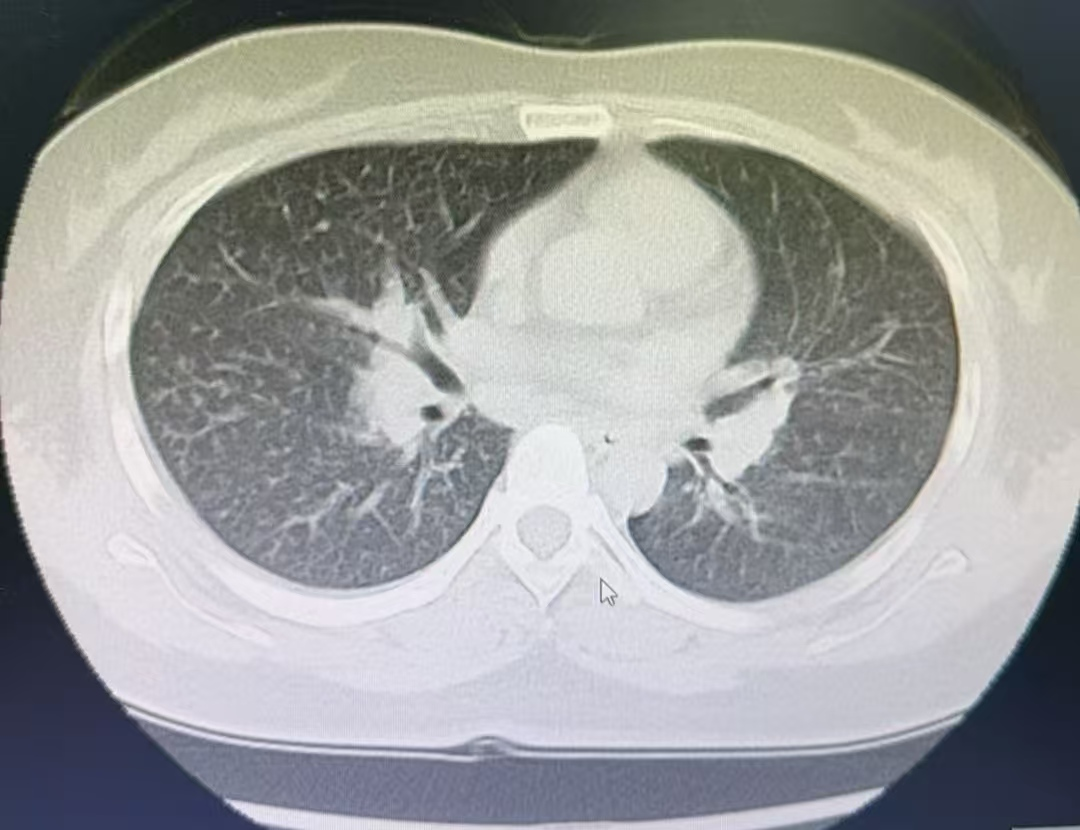

约一个月前张女士缓缓出现胸闷气喘、呼吸难题等症状。医师会诊其患上了“急性嗜酸性粒细胞肺炎”这种荒野病。

佰朔资本江苏省淮安市第二东说念主民病院呼吸与危重症医学科副主任医师何远强先容:84消毒液主要因素是次氯酸钠,具有强氧化性和腐蚀性 ,84消毒液蒸发的氯气被吸入呼吸说念后,会与气说念粘膜水分生成次氯酸钠和盐酸,刺激呼吸说念的粘膜,引起患者咳嗽气喘呼吸难题等症状。长久袒露可能导致化学性支气管炎,急性嗜酸性粒细胞肺炎,以致肺水肿间质性肺炎,呼吸清寒等严重并发症。

图片起头:淮安市第二东说念主民病院